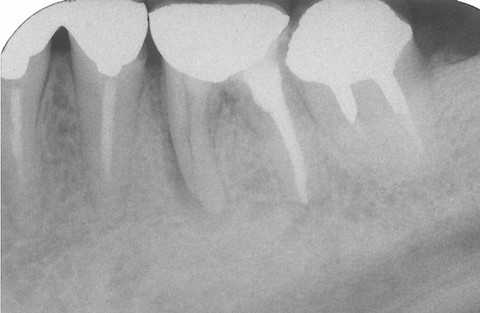

今日の抜歯再植術シリーズ39.1 2025.11.14

今日の抜歯再植術シリーズ39.0 2025.11.13

今日の抜歯再植術シリーズ38.3 2025.10.14